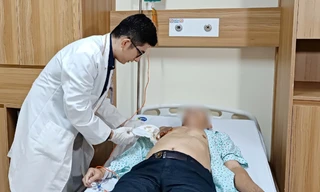

Một số đau vai gáy là bệnh lý ngoại khoa cần can thiệp; một số đau vai gáy là bệnh lý nội tiết chuyên khoa sâu; đôi khi lại cần can thiệp kĩ thuật của chuyên khoa tim mạch…Do vậy, người bệnh không nên vội điều trị khi chưa khám bác sĩ.

| Một số đau vai gáy là bệnh lý ngoại khoa cần can thiệp; một số đau vai gáy là bệnh lý nội tiết chuyên khoa sâu; đôi khi lại cần can thiệp kĩ thuật của chuyên khoa tim mạch…Do vậy, người bệnh không nên vội điều trị khi chưa khám bác sĩ. Ảnh minh họa: Internet |